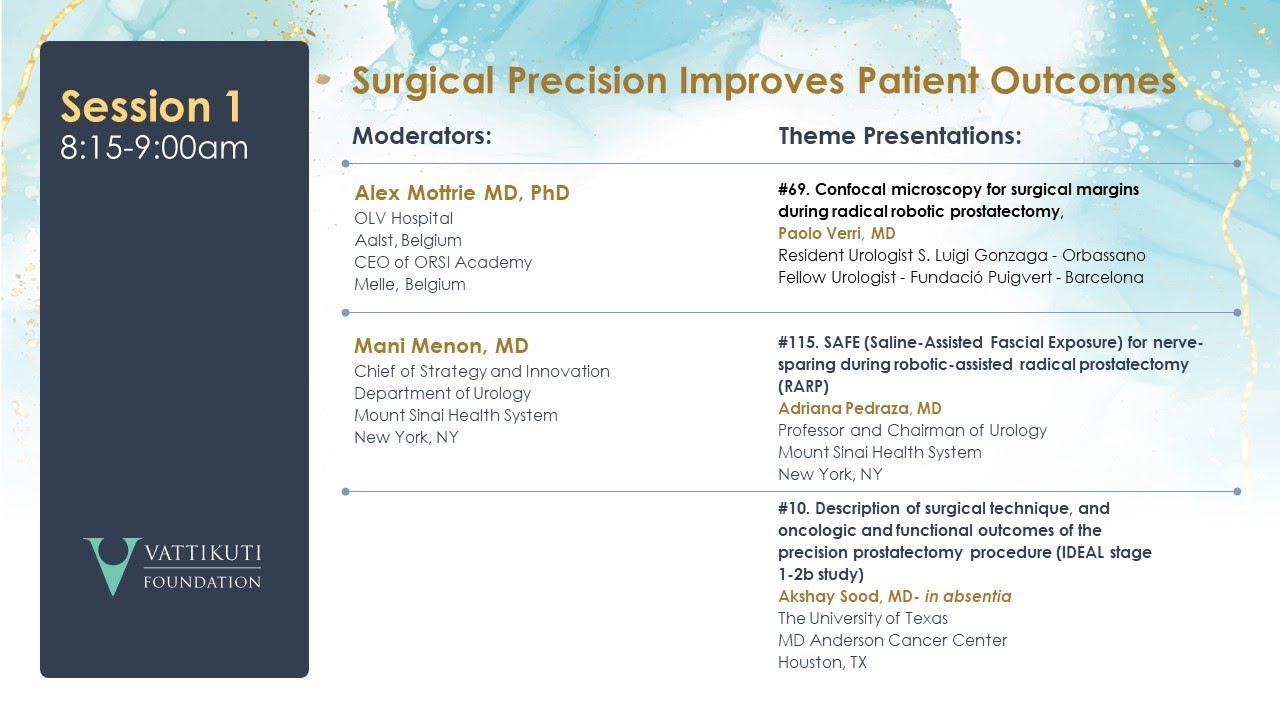

SAFE (Saline-Assisted Fascial Exposure) for Nerve-Sparing during RARP

Confocal Microscopy for Surgical Margins During Prostatectomy